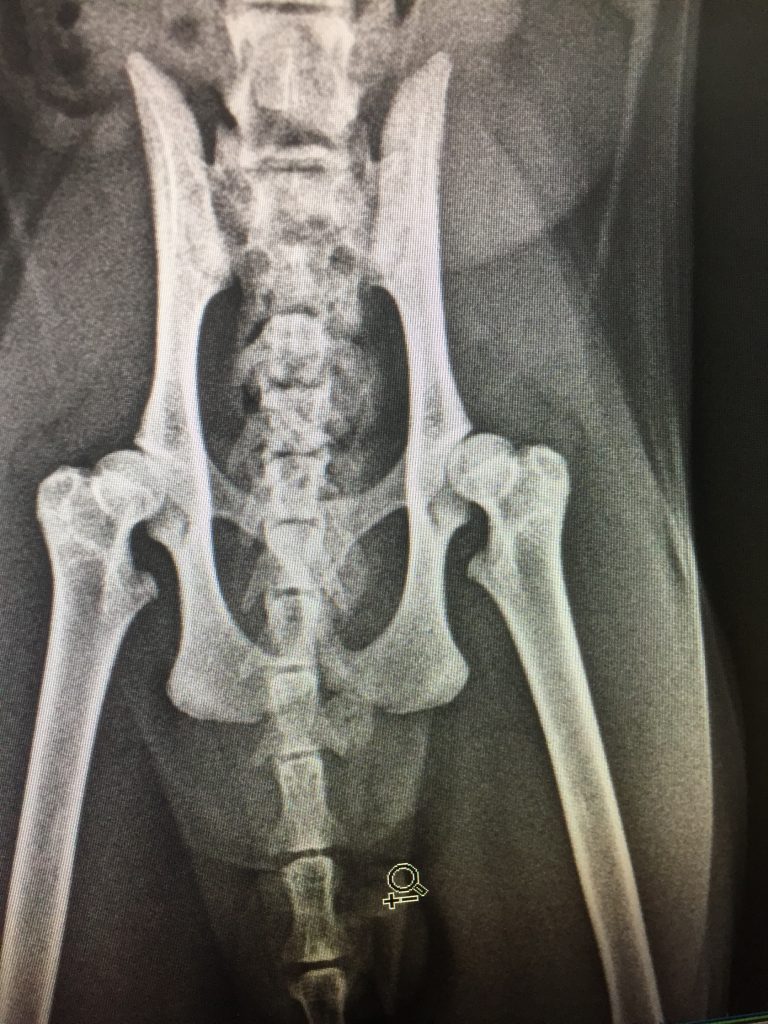

Vaka 1 yaş scottish fold arka sağ bacakta uzun süreli topallık ve nesef alma güçlüğü.

grafisinde hem sol hemde sağ ayakta dizplazik durum tespit edildi. (röntgen resimlerde var) Genetik ve konjenital nedenlere bağlı. Herhangi bir travma yok.

Caput Femoris Rezeksiyonu (Excision Arthroplasty)

Sonuç operasyon başarılı. sağ arka femur başı alındı. 2 ay sonrasına diğer bacak için operasyon kararlaştırıldı.